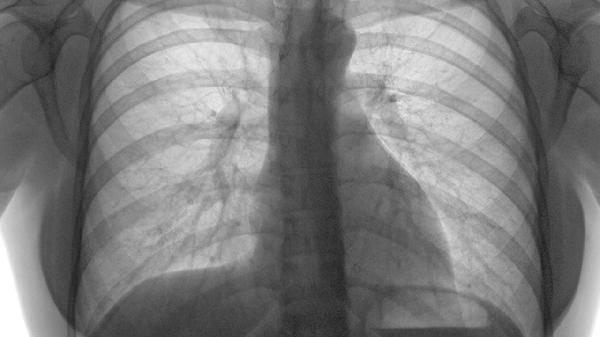

肋软骨炎患者除药物治疗外,应避免胸部剧烈运动或负重,可局部热敷促进血液循环。睡眠时选择仰卧或健侧卧位减轻患侧压力,均衡饮食补充蛋白质和维生素C有助于组织修复。若疼痛持续超过两周或伴随发热、呼吸困难等症状,需及时复查排除其他胸廓疾病。所有药物均需在医生指导下使用,不可自行增减剂量或更换药物。